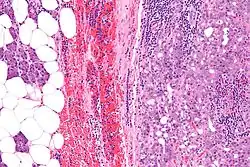

| Micrograph of an acinic cell carcinoma (right of image) and acinar glands (parotid gland - left of image). H&E stain. | |

Histopathologic features

Basophilic, bland cells similar to acinar cells. Growth pattern: solid - acinar cells, microcytic - small cystic spaces mucinous or eosinophilic, papillary-cystic - large cystic lined by epithelium, follicular - similar to thyroid tissue.

These tumors, which resemble serous acinar cells, vary in their behavior from locally aggressive to blatantly malignant.